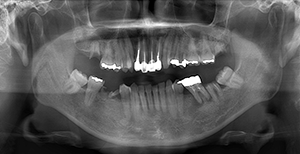

図❶ 初診時のパノラマX線写真

画像所見:パノラマX線写真にて左側上下顎に残根、根尖病巣を認めるが、下顎頭の変形、骨破壊像などは認められなかった(図❶)。